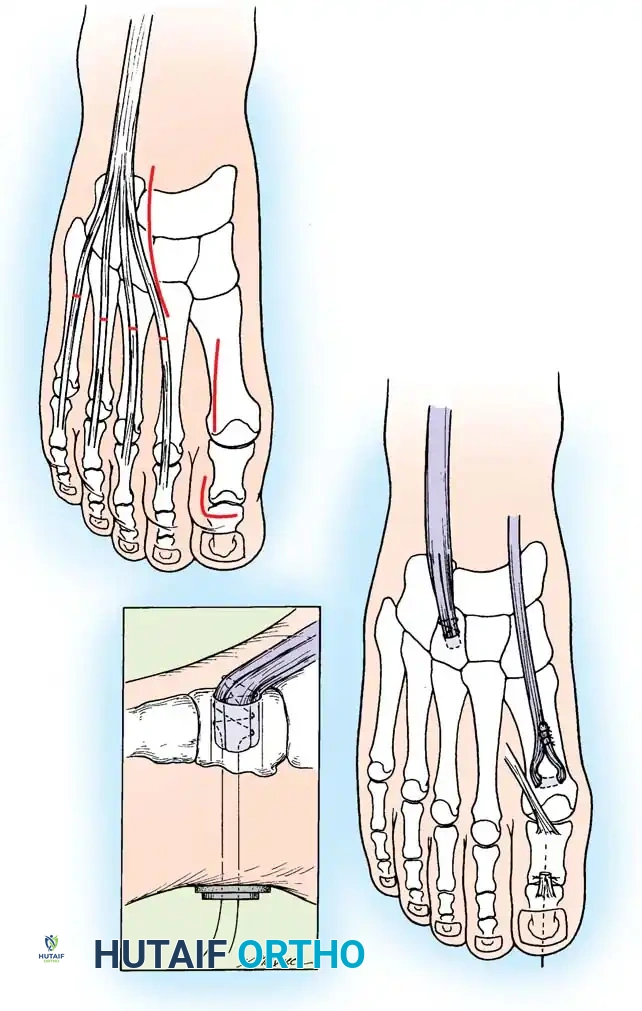

1. First Metatarsal Dorsiflexion Osteotomy

* Indications: Rigid plantarflexed first ray.

* Approach: Dorsal longitudinal incision over the proximal first metatarsal.

* Osteotomy: Protect the extensor hallucis longus (EHL) tendon. Perform a dorsal closing-wedge osteotomy approximately 1.5 cm distal to the tarsometatarsal joint.

* Fixation: Elevate the metatarsal head to neutral alignment with the lesser metatarsals. Fixate with a dorsal titanium plate, crossed K-wires, or a compression staple.

Fig. 8: Planning the dorsal closing wedge osteotomy of the first metatarsal to correct forefoot equinus.

2. Jones Procedure (EHL to First Metatarsal Neck)

* Rationale: Corrects flexible clawing of the hallux and elevates the first ray.

* Technique: Transect the EHL at the IP joint. Reroute it through a drill hole in the neck of the first metatarsal and suture it back onto itself. The IP joint of the hallux must be arthrodesed to prevent a secondary drop-toe deformity.

Fig. 9: Biomechanical routing for tendon transfers in the correction of claw toe and forefoot equinus.